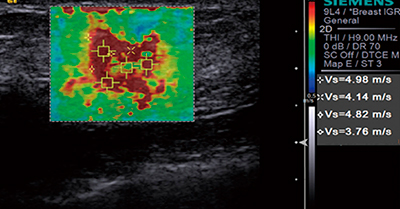

●Virtual Touch Technology

音響放射力を応用して,より客観的な組織硬度の情報を提供します(図3)。用手的な加振が不要であるため,操作者の手技に依存するところが少ないエラストグラフィです。

視覚的な組織弾性イメージングとシアウェーブ伝搬速度で,局所の組織硬度を評価する定量測定が可能です。

図3 Virtual Touch Technology